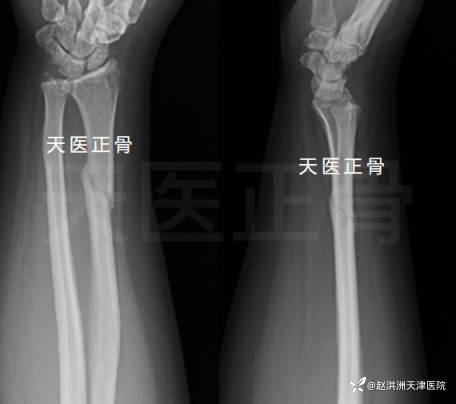

骨折的定义:主持人解释说,骨折就是骨头断裂,分为完全骨折和部分骨折两种。完全骨折是指骨头完全断裂,部分骨折是指骨头部分断裂。

治疗方法:视频介绍了骨折的治疗方法,包括保守治疗和手术治疗。保守治疗主要包括休息、固定、药物治疗等;手术治疗则适用于严重骨折或合并其他疾病的患者。